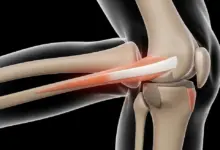

Nas rupturas completas, a cirurgia costuma ser parte importante do tratamento, pois o tendão perde a continuidade, e o joelho deixa de executar adequadamente a extensão ativa da perna.

O objetivo é restaurar o mecanismo extensor e devolver segurança ao joelho.

Os quadros mais lembrados envolvem o tendão patelar e o tendão do quadríceps, ambos fundamentais para o mecanismo extensor do joelho.